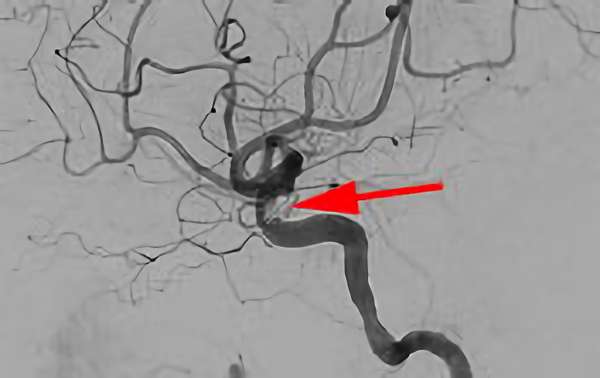

No.1631 手術前